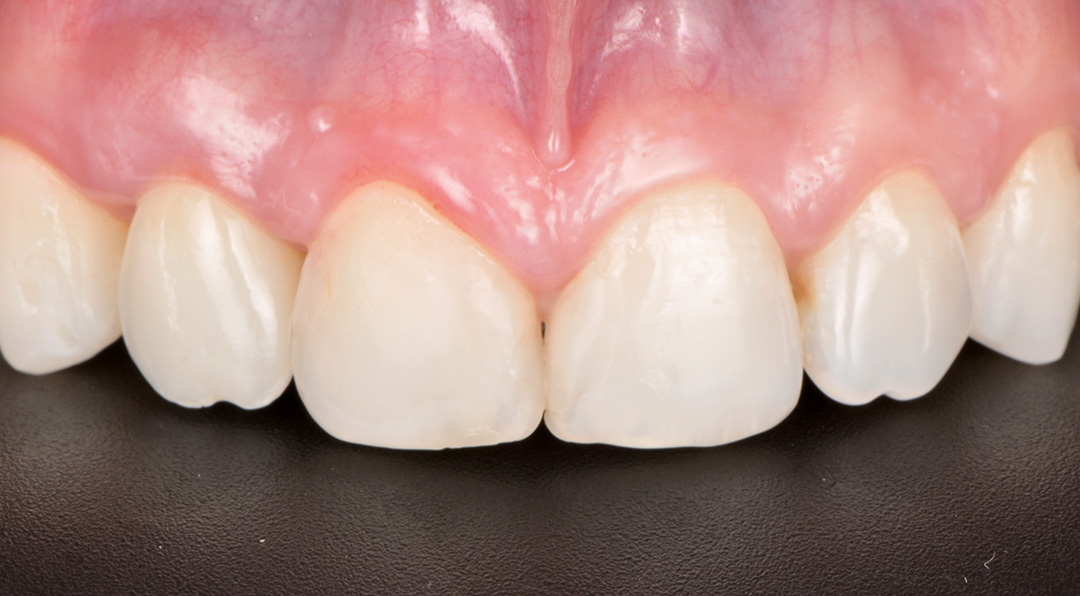

Four months post-placement, the implant site exhibited stable soft tissue contours and full graft integration. A screw-retained lithium disilicate crown was delivered and bonded to a customised anodised titanium abutment. Radiographs confirmed excellent osseointegration and bone preservation. Post-operative care included chlorhexidine 0.12% gel application twice daily for 14 days. The patient expressed high satisfaction with the aesthetic result, and no recession or tissue shrinkage was observed during the healing period.

Surgical healing was uneventful and the patient reported no pain or discomfort. Papillae remained healthy and filled the embrasures completely. A final zirconia restoration was ultimately placed, designed to slightly alter the over-contoured emergence profile from the exocad software. This simplified the fitting protocol and further prevented the collapse of the hard or soft tissue during the final healing phase.